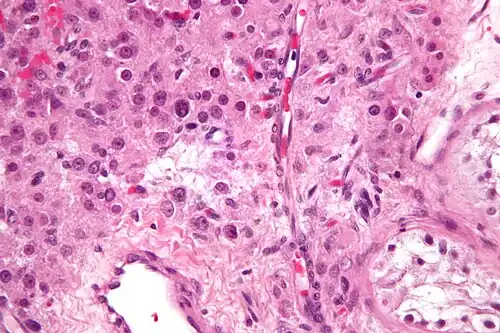

| Micrograph of a granulosa cell tumour, a type of sex-cord–gonadal stromal tumour. H&E stain. | |